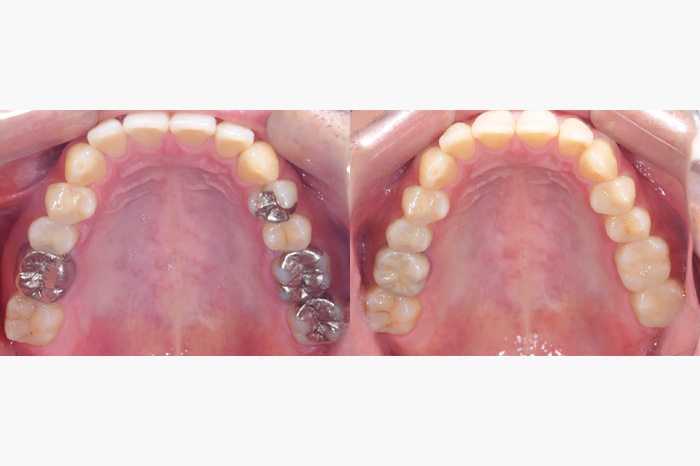

| 年齢 | 30代・女性 |

| 主訴 | 銀歯がきになる |

| 治療内容 | 右上奥歯の銀歯のブリッジを除去し、ジルコニアのインレーとクラウンとポンティックを組み合わせたジルコニアブリッジを作成しま した。 |

| 治療費 | ジルコニアブリッジ: 165,000円(税込) |

| 治療期間 | 1ヶ月 |

| リスク・副作用 | ブリッジは歯を多く削る治療になりますので、治療後にしみる可能性が高くなります。必要に応じて神経をとらないといけなくなることもあります。 |